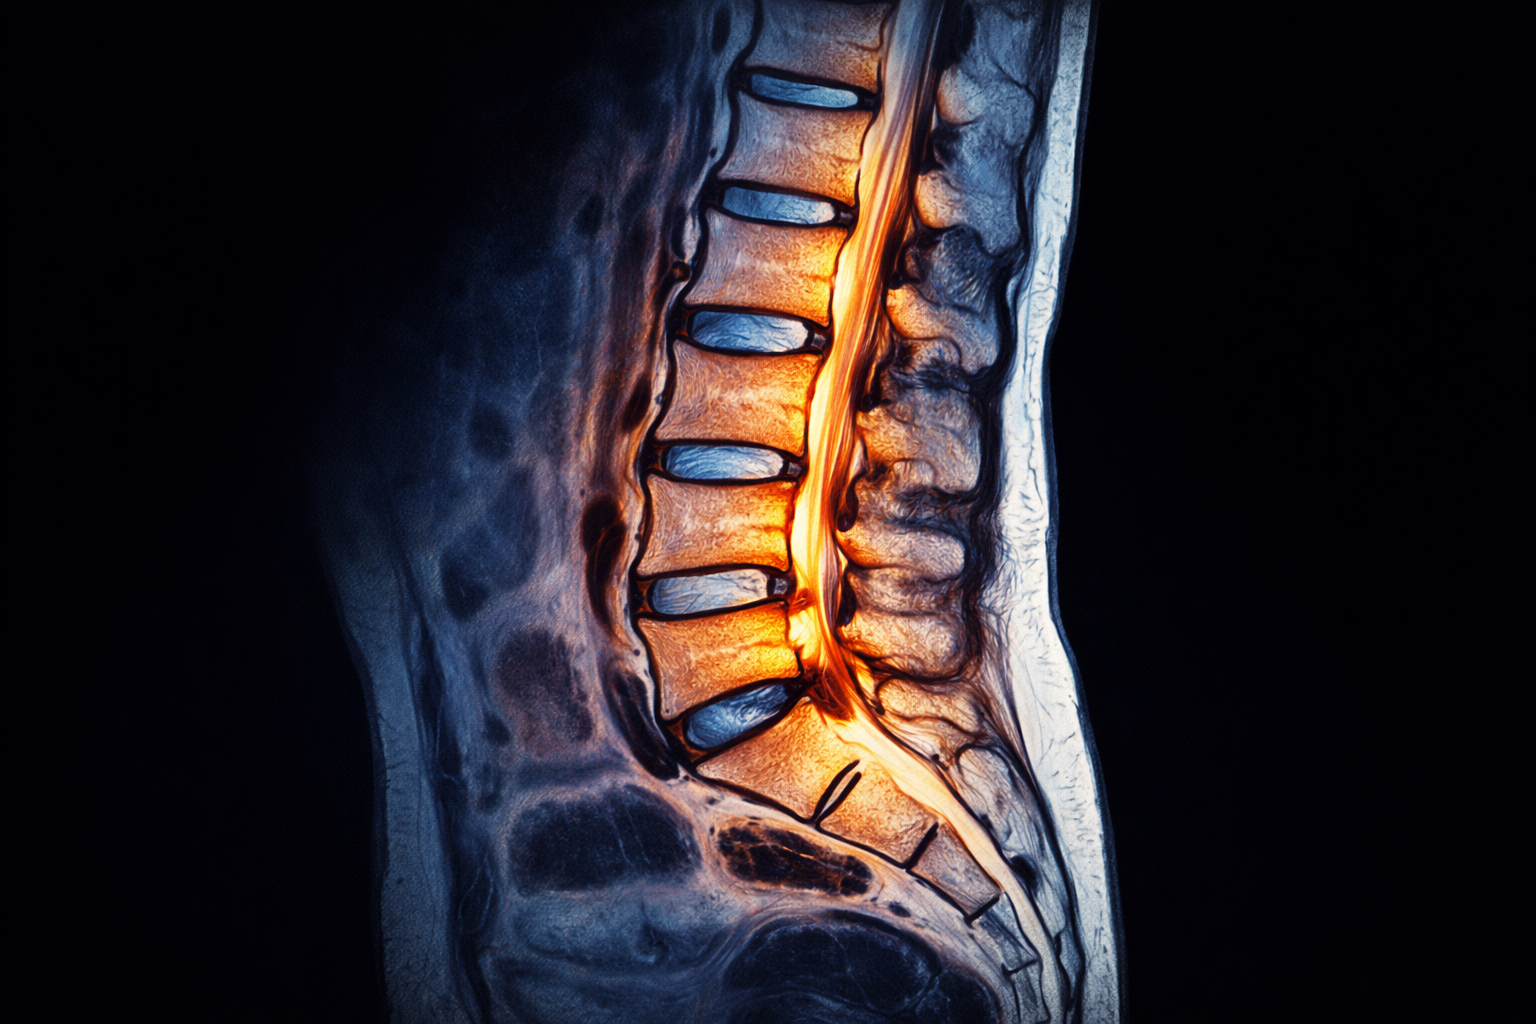

MRI lumbalno-sakralne kičme (donji dio kičme) je savremena i izuzetno precizna dijagnostička metoda koja omogućava detaljan prikaz struktura donjeg dijela kičme, uključujući pršljenove, diskove, nerve i okolna meka tkiva. Ovaj pregled je ključan u otkrivanju uzroka bolova u donjem dijelu leđa, koji su među najčešćim zdravstvenim problemima. Zahvaljujući visokoj rezoluciji, MRI omogućava rano otkrivanje degenerativnih promjena i oštećenja. Pregled je bezbolan, ne koristi zračenje i predstavlja zlatni standard u dijagnostici kičmenih problema.

MRI lumbalno-sakralne kičme omogućava detaljan prikaz svih struktura donjeg dijela kičme. Jasno prikazuje diskus hernije, degenerativne promjene na diskovima i suženje spinalnog kanala. Također omogućava uvid u stanje živaca, što je ključno kod bolova koji se šire u noge. MRI može otkriti i upalne procese, tumore ili druge promjene koje uzrokuju bol i nelagodu. Ova preciznost omogućava tačnu dijagnozu i pravilan izbor terapije.